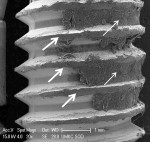

+++ Mostly effective treatment = removal of cement from crest of implant threads and most of the cement between threads, with exposure of most of the subjacent implant surface (Figure 6 and Figure 7).

The CO2 9300 nm laser visibly removed most of the cement on all three implant surfaces and showed minimal surface changes under SEM (Figure 6 and Figure 7), while the Er,Cr:YSGG and Er:YAG lasers and the Nd:YAG laser alone had a minimal effect on the cement and implant surface (Figure 2 and Figure 3). Cement removal by the CO2 10,600 nm laser as a monotherapy was variable depending on the surface tested.

Table 1 reveals that none of the treatment modalities was completely successful at removing all cement from the implant test surfaces. Post-treatment SEM evaluation was carried out to obtain magnified views of residual cement and assess damage to the implant surface that might have occurred as a result of treatment. The effectiveness of cement removal varied markedly, with the implants treated with the CO2 9,300 nm laser protocol being mostly free of cement (Figure 6 and Figure 7) and the Er,Cr:YSGG and Er:YAG lasers (Figure 2 and Figure 3) and Nd:YAG laser (as a monotherapy) being minimally effective. When used as part of a dual therapy in conjunction with the piezo scaler, the Nd:YAG, CO2 10,600 nm, and diode lasers were only marginally more effective than the piezo scaler alone.

The CO2 9,300 nm laser was the most promising treatment tested and deserves further evaluation. It removed most of the cement on all three implant surfaces and inflicted little to no surface changes.